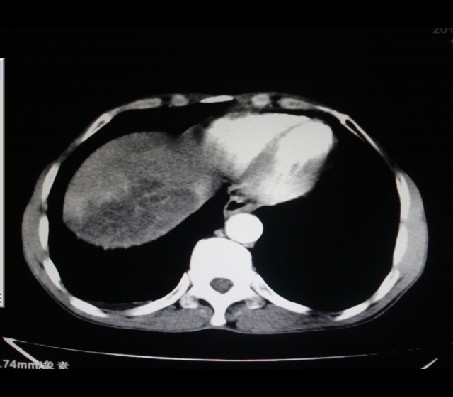

男性,62岁。肝右叶占位,平扫及增强如下,延迟期为15分钟扫描。

给病史及实验室检查!多考虑胆管细胞癌;右肾囊肿。

1)不均匀性脂肪肝。2)肝硬化。3)肝右叶肝癌不排除。4)右肾囊肿。

延迟期怎么进去了   血管瘤?